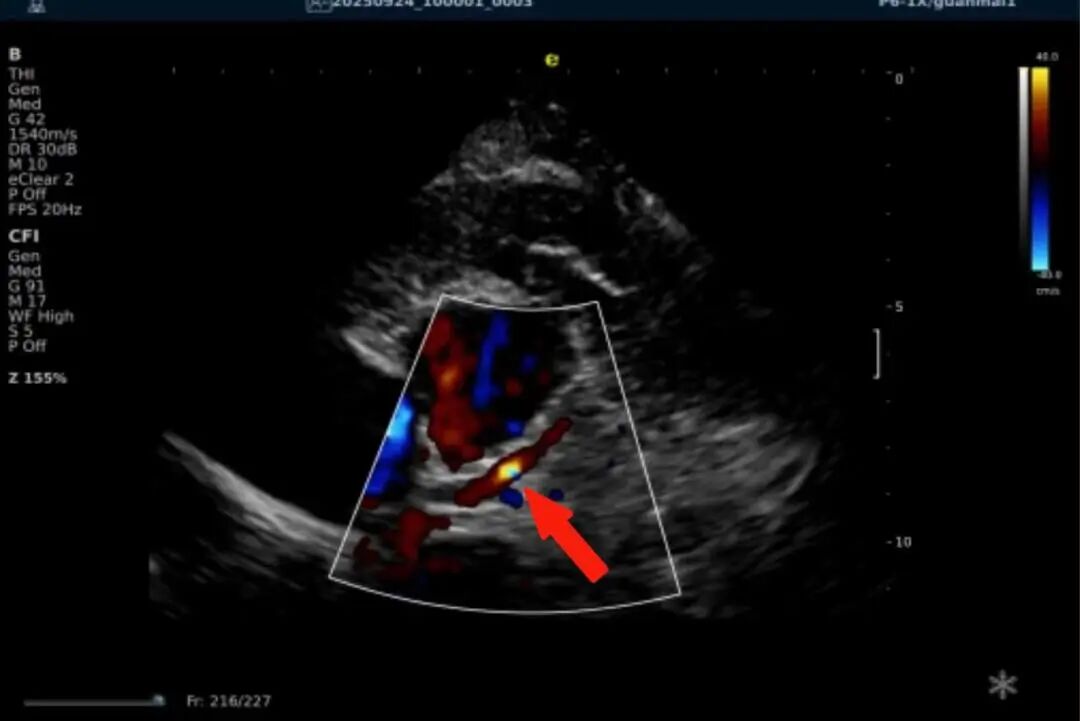

一例胸闷患者,临床采用无创冠脉超声作为初步评估手段,检查中发现:

彩色多普勒:敏感捕捉到局部血流加速现象;频谱多普勒:测得峰值血流速度明显升高,频谱形态异常。

彩色多普勒动态图

彩色多普勒

基于超声提示的异常发现,临床为患者安排了冠脉CTA检查,结果显示前降支近段存在约45%狭窄,与超声提示的血流动力学改变高度一致。

这一病例体现了冠脉超声作为初筛工具的重要价值:它能够无创、实时地评估冠脉血流动力学状态,为后续是否需要进一步影像检查提供重要参考。超声与CTA的协同应用,既能评估结构变化,又能反映功能状态,为临床诊断提供了更全面的信息。